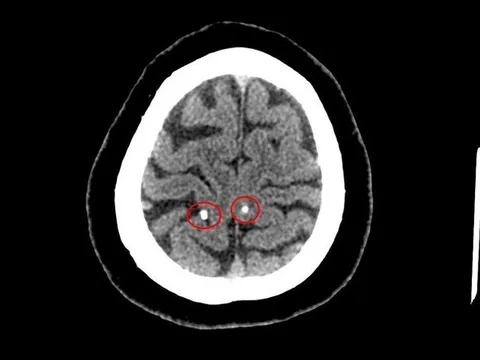

Sán làm tổ trong não vì thói quen ăn đồ sống

Đi khám vì thấy nhức đầu nhiều, người bệnh được chụp cắt lớp vi tính sọ não, kết quả cho thấy hình ảnh nang ký sinh trùng trong não.